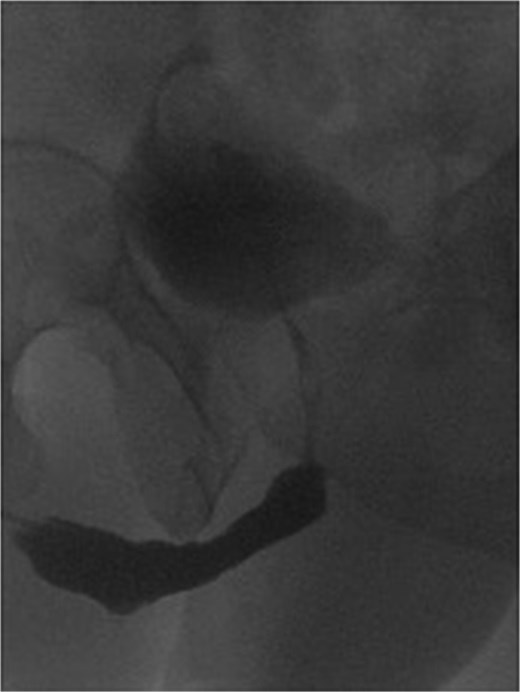

The patient was able to void freely through the urethra and was kept on CIC to ensure low post-void residual volume, which led to the successful surgical closure of the Mitrofanoff stoma. At five-year follow-up, there was no evidence of recurrence of his disease, and his course was satisfactory. CIC was discontinued entirely over the last 2 years. His renal function remained stable with minimal post-void residuals. Cystourethroscopy confirmed a wide, healthy urethra at the graft site, without recurrence, blistering or ulceration. Follow-up urethrogram confirmed a patent repair without evidence of leak or stricture recurrence, and contrast reaching easily to the bladder (Fig. 2).

Post buccal graft mucosal urethroplasty urethrogram, showing wide urethra at the site of repair without recurrence.